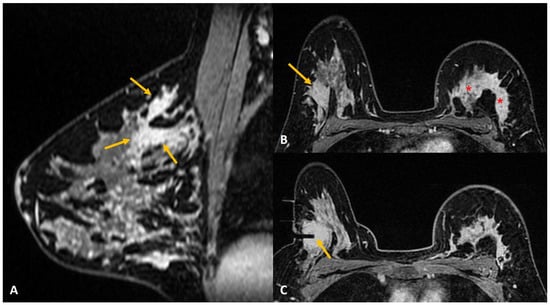

Figure 2.

(A). Staging MRI in a woman with known left breast cancer (red asterisk) showed focal non-mass enhancement in the right breast (yellow arrow). (B). MRI-guided biopsy to rule out contralateral synchronous cancer showed the tip of the obturator at the right location (yellow arrow). (C). Post-biopsy non-fat saturated image showed a large hematoma at the biopsy site almost occupying the upper outer quadrant (yellow arrow). (D). Tight compression bandage applied to the breast after the biopsy reduces the risk of further bleeding significantly.